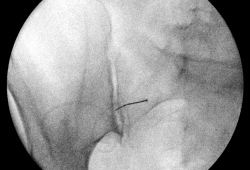

Op de recovery wordt er voor de behandeling een infuus geplaatst. Eénmaal in de behandelzaal neemt u op de buik plaats op de behandeltafel. Na ontsmetting van de huid wordt het gewricht onder begeleiding van röntgendoorlichting of echografie aangeprikt met een fijn naaldje. De huid wordt eerst lokaal verdoofd. Daarna wordt contraststof ingespoten om de juiste positie te controleren, gevolgd door een mengsel van verdoving en een ontstekingsremmer (corticosteroïd).